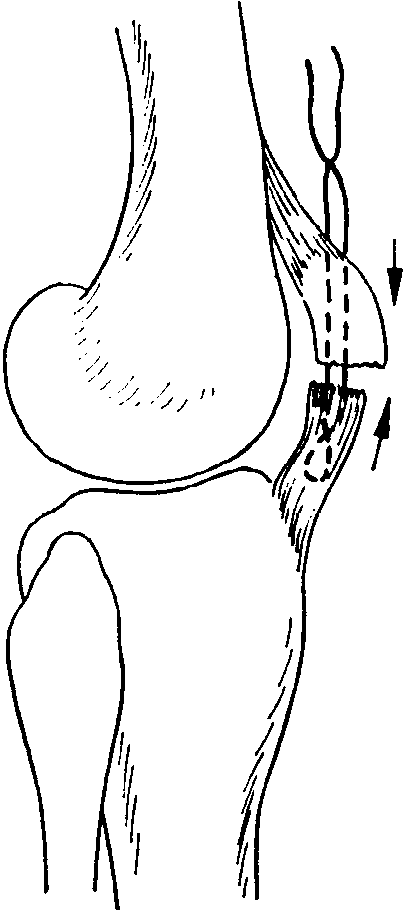

Как фиксируют надколенник? Вариант остеосинтеза определяется типом перелома. При поперечном переломе сопоставить и скрепить отломки можно с посощью специальной медицинской проволоки (серкляжа) и спиц. Такую операцию называют именем ее изобретателя – Вебера.

Если имеется отрывной перелом нижнего края надколенника, при котором линия перелома не проходит по суставной поверхности, то этот маленький отломок просто убирают (частичная пателлэктомия), подшивая связку надколенника.

Оперативное лечение показано при переломах надколенника с расхождением отломков более чем на полсантиметра. При этом чаще всего пользуются методом Берже-Шультце, при котором после разреза мягких тканей удаляют сгустки крови, сближают отломки, на разорванные боковые связки накладывают швы. После этого мягкие ткани надколенника вокруг него прошивают нитями (одна нить сверху, другая снизу), захватывающими глубокие ткани. Срок иммобилизации после такой операции — около месяца, после чего назначают физиотерапевтические процедуры и массаж.

Наиболее распространённый способ фиксации – это остеосинтез по Веберу, хирургу, который придумал эту операцию. При этой операции для фиксации используются спицы и проволока (продемонстрировано на схеме ниже).